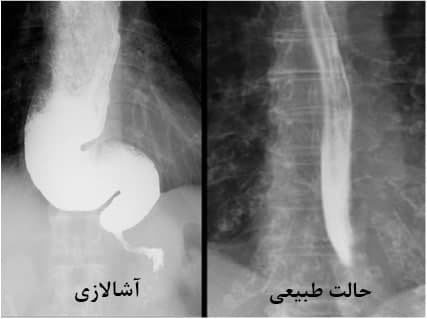

2. بلع باریم: بیمار ماده‌ای به نام باریم می‌نوشد و با استفاده از تصویربرداری رادیولوژی، حرکت باریم در مری بررسی می‌شود.

3. بلع باریم: تصویربرداری رادیولوژی که حرکت ماده کنتراست در مری را نشان می‌دهد.